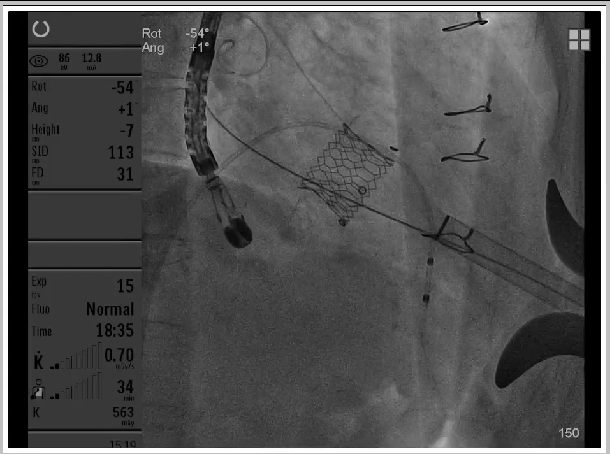

25#Renatus瓣膜释放

Atlas Gold球囊高压力后扩,扩断25#Mosaic瓣膜

瓣膜释放后状态

第一次高压球扩后形态

第二次高压球扩后形态